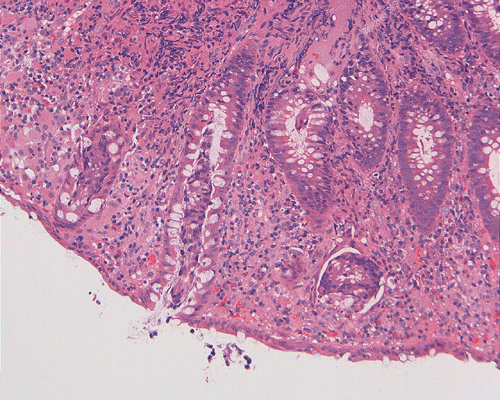

On low-magnification, the biopsy appears to be a piece of colonic mucosa without evidence of necrosis, erosion, or ulcer (Panel A). On medium-magnification, the lamina contains some vaguely formed collections of large cells (Ú in Panel B). On high-magnification, there are many large, round cells with eccentric nuclei. These are macrophages in clusters that are consistent with granulomas.  Many small, grayish to basophilic, vesicle-like structures are present in the cytoplasm (Panel in C). In other areas, these large, round cells do not really form small clusters and are admixed with lymphocytes (Panel D). Again, many small, grayish vesicle-like structures are present in these cells. A grayish to basophilic core is present and is surrounded by halo (Ú in Panel E).  These structures are most suggestive of microorganisms particularly fungus. On periodic acid Schiff (PAS), these vesicles appear bright purple-red (Panel F and G). The basophilic core is also strongly positive for PAS stain (Panel G). These microorganisms appear dark with Gomori methamine silver stain (Panel H and I).

Comment: The pathologic changes in this case are morphologically consistent with histoplasmosis. The patient is immunocomrpomised (HIV-2 positive). Typical to these cases are poorly formed granuloma as illustrated in this case.

DIAGNOSIS: Histoplasmosis (in an HIV seropositive patient) of colon.

In immunocomprised patients that have defective cellular immunity, granuloma formation may be rather indistinct as illustrated in our case. The yeast form of Histoplasma capsulatum is found in tissue and they are usually under 5 mm in diameter and appear as ovoid yeasts.  The lung is the most affected organ. Granuloma formation, typically multiple, with extensive caseous necrosis and a variable amount of calcifications are the typical pathologic changes in the lung. These granulomas are often demarcted from the surrounding tissue by a fibrous wall. Granulomas in the lung can get quite calcified with time. The pulmonary nodules can also enlarge slowly to give a wrongful clinical impression of neoplasm, the so-called histoplasmoma. The living yeast in tissue, often occur in clusters, has a basophilic center and a translucent halo that represents the capsule. They are often engulfed by histiocytes as illustrated in this case. Dead organisms appear eosinophilic and cannot be detected easily in granuloma by hematoxylinj-eosin stain. The microorganism is numerous and can be identified on routine hematoxylin-eosin stain with astute observation and high index of suspicion. Typically, there are numerous yeasts and they are present even in heavily calcified nodules or granulomas.